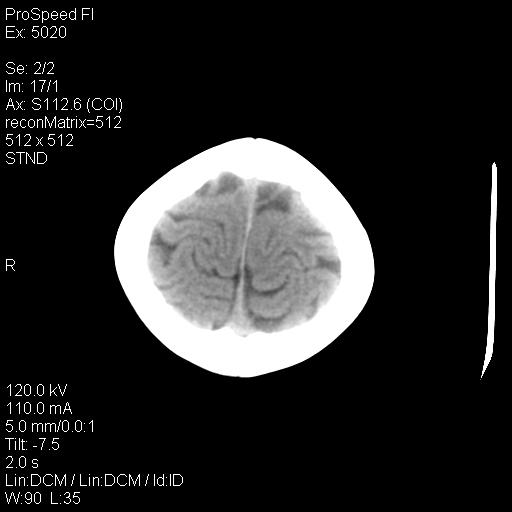

标题: PED1637:M 6Y 顶部无痛性包块两月。 [打印本页]

标题: PED1637:M 6Y 顶部无痛性包块两月。

2、颅骨皮样囊肿,皮样囊肿内为脂肪密度ct值多为负值,常在-15~10hu之间。

3、颅骨表皮样囊肿 病灶常有完整的包膜,ct值高低不等,可为脂肪密度至软组织密度,ct值常在-70—120hu之间。

事发冠状缝与矢状缝交界区,密度较低,考虑表皮样囊肿可能性大,其次不除外嗜酸性肉芽肿